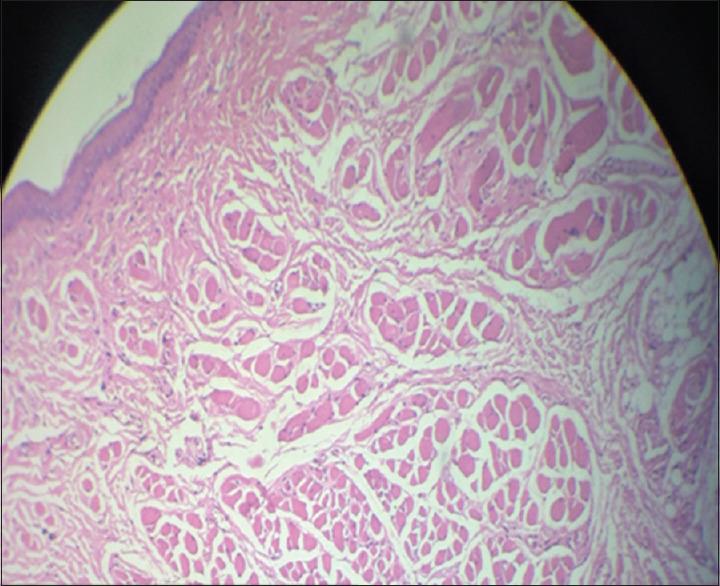

Oral submucous fibrosis was induced by submucosal injection of arecoline in the buccal mucosa. Arecoline hydrochloride at a dosage of 10 mg/kg was injected into the submucosa of right buccal mucosa in experimental animals over a period of 3 months on every alternate day. After which, right buccal mucosa, gastrointestinal tract organs like stomach, large intestine, small intestine and liver were dissected, subjected to histopathological evaluation of the healthy and experimental Wistar rats were subjected to histopathological evaluation.

On histological evaluation, OSMF was seen to affect Wistar rats showed significant changes in oral mucosa, decrease number of goblet cells in the small intestine as well in the large intestine and deranged hepatocytes. These marked changes indicated a definite effect on the gastro intestinal system by arecoline.